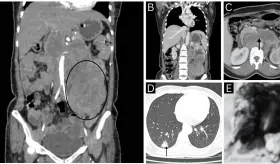

La joven inicialmente fue diagnosticada con anemia, pero en realidad padecía de algo mucho más grave.